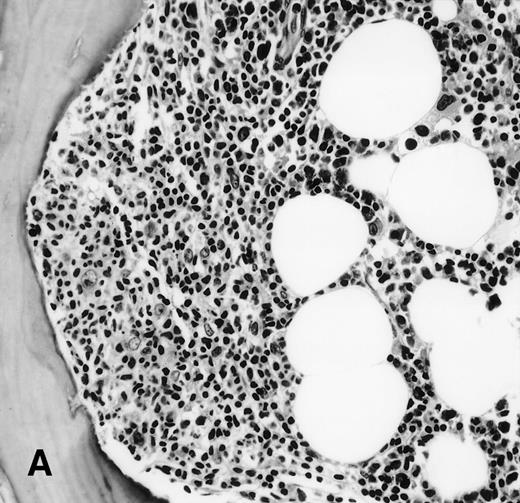

It is the remaining 15 cases that deserve additional description. Ten cases demonstrated morphologic features of lymphoma on the BM biopsy specimen and were confirmed by immunohistochemical staining, but had a polyclonal B-cell immunophenotypic pattern. Subgating based on cell size and backgating with CD19 or other antibodies failed to identify a monoclonal or abnormal B-cell population. κ/λ ratios ranged from 0.20 to 1.8:1 in these 10 cases. Five of the 10 cases were from patients with follicular lymphoma, predominantly small cleaved type, and 5 were from patients with large-cell lymphoma (Fig 1). One of the latter 5 patients with large-cell lymphoma had a discordant BM morphology with primarily a small, cleaved cell infiltrate seen in the BM sections. In addition to morphologic features indicative of lymphoma, all 10 cases demonstrated a prominent CD20+, lymphomatous infiltrate by immunohistochemistry on paraffin sections of the marrow biopsies. The extent of involvement by lymphoma in these cases was quite variable, with 4 showing small, focal, paratrabecular patterns of infiltration; 4 showing less than 20% involvement in a random, nodular pattern; and 2 cases with single, albeit relatively large, foci. It seems reasonable to conclude that the discordance seen in these 10 cases may be ascribed to either variation in sampling between the aspirate and biopsy, the minimal marrow disease seen in some biopsies and not represented in the aspirate specimen, or failure to aspirate the diagnostic cells due to reticulin fibrosis that can be associated with a lymphomatous infiltrate.16 28

(A) BM biopsy showing a paratrabecular lymphoid infiltrate of atypical lymphoid cells, diagnostic of involvement by malignant lymphoma and confirmed by CD20+immunohistochemical staining. A lymph node biopsy showed a follicular lymphoma. Flow cytometric studies demonstrated polyclonal B cells with no monoclonal B-cell population identified (H&E; original magnification × 400). (B) BM biopsy showing a nodular lymphoid infiltrate of atypical, large lymphoid cells, diagnostic of involvement by malignant lymphoma and confirmed by CD20+ immunohistochemical staining. A lymph node biopsy showed a large-cell lymphoma. Flow cytometric studies of the marrow aspirate demonstrated polyclonal B cells with no monoclonal B-cell population identified (H&E; original magnification ×400).